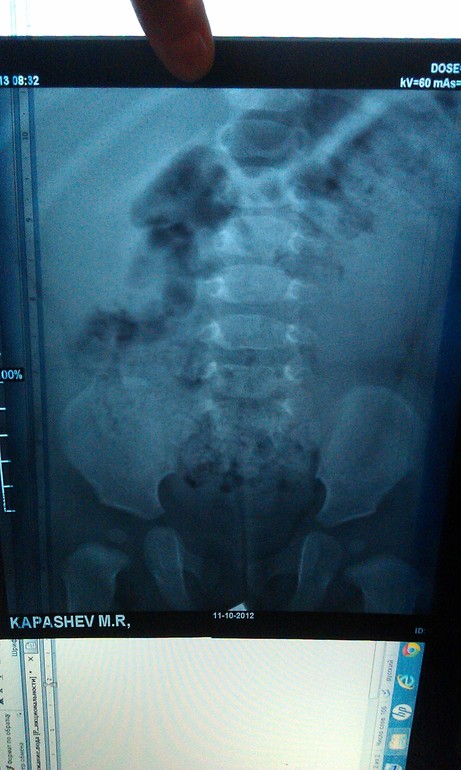

Урография

Максиим Викторович. Если возможно, могли бы вы прокомментировать нашу урограмму. Заключение рентгенологов и урологов разнятся. Хотелось бы послушать мнение третьего специалиста.

Олеся, я бы с радостью, но так снимки объективно оценить не смогу, тем более не зная клинической ситуации. Слева понятно, а с правой почкой что?